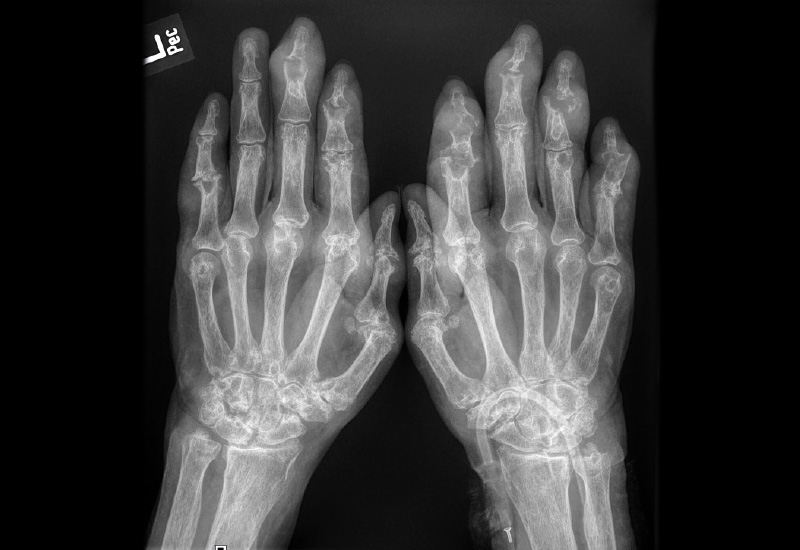

RÖNTGEN: Im Gegensatz zur Sonografie wird das Röntgen hauptsächlich in späteren Stadien der tophösen Gicht eingesetzt, um fortgeschrittene Veränderungen zu dokumentieren. Typische Röntgenbefunde sind Knochenläsionen und Erosionen, die durch die Ablagerung von Harnsäurekristallen verursacht werden. Tophusablagerungen können ebenfalls sichtbar werden, oft als weiße, dichte Areale in den Weichteilen um das Gelenk. Röntgenaufnahmen liefern Informationen über Gelenkschäden und Deformitäten, sind jedoch weniger empfindlich für die frühzeitige Erkennung von Gicht im Vergleich zur Sonografie.